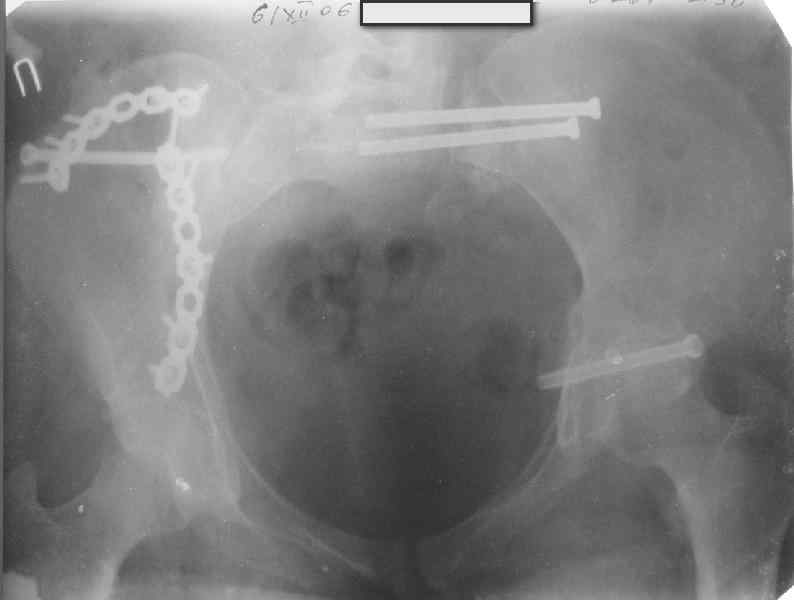

Молодая девушка 19 лет, травма 1 год назад, тогда же прооперирована.

В настоящее время имеются ноющие боли в области крестца слева, нарушение походки, ощущение неуверенности, слабости в левой нижней конечности, неврологически -непостоянные парестезии в левой нижней конечности. Ходит с дополнительной опорой, страдает от ожирения.

В приложении снимки при поступлении и послеоперационные год назад.

Могу сказать одно: миграция винтов и нестабильность синтеза левого подвздошно-крестцовогоо сочленения очевидна.

были использованы винты 7.2 мм, кроме того иетодика транссакральной фиксации не является общепринятой и широко рекомендуемой, но и в этих случаях они наблюдали случаи вторичного смещения